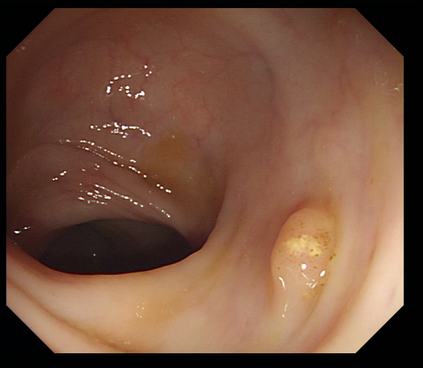

Deep learning has shown excellent performance in analysing medical images. However, datasets are difficult to obtain due privacy issues, standardization problems, and lack of annotations. We address these problems by producing realistic synthetic images using a combination of 3D technologies and generative adversarial networks. We use zero annotations from medical professionals in our pipeline. Our fully unsupervised method achieves promising results on five real polyp segmentation datasets. As a part of this study we release Synth-Colon, an entirely synthetic dataset that includes 20000 realistic colon images and additional details about depth and 3D geometry: https://enric1994.github.io/synth-colon